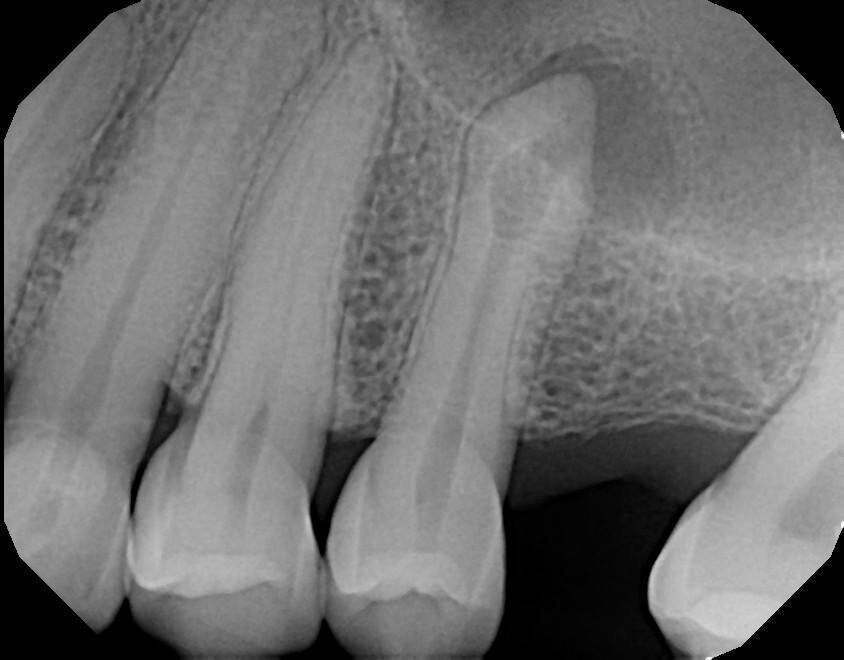

Fig. 18a: Note the expert management of the apical constriction and the acute curvature of the MB root. (Courtesy of Dr. Nestor Cohenca)

Fig. 18b: Note the expert management of the apical constriction and the acute curvature of the MB root. (Courtesy of Dr. Nestor Cohenca)

Fig. 18c: Note the expert management of the apical constriction and the acute curvature of the MB root (courtesy of Dr. Nestor Cohenca).

Goals of canal preparation include keeping the canal centered in its original position within the root structure and keeping the apical foramen at its original position and size. One of the hallmarks of all the cases illustrated is that the apical foramen has been respected. Specifically, it has not been moved, transported, zipped and/or altered in any way. The apical foramen might be thought of as the “North Star” in endodontics. Reaching the apical constriction without transporting the canal and eliminating all debris from the canal and providing a tapering funnel from orifice to apex is a key canal preparation objective.

The final prepared canal shape should be large enough to irrigate and obturate, but not so large as to structurally weaken the tooth. For practical purposes, while treatment philosophies differ, the minimum guidelines for final prepared taper should be .04 and the minimum apical diameter a 30 (depending on the initial size of the foramen). Given the advent of controlled memory nickel titanium there is little indication for larger tapers, especially in fine three-dimensional apical curvatures. As mentioned, patency is essential because its obtainment means that the clinician can always reach the apex during every phase of treatment and its loss means that tissue, toxins and bacteria can remain despite irrigation procedures, especially in the apical third. Apical debris is the harbinger of iatrogenic events including but not limited to canal transportation, zipping, irrigant extrusion and a lack of optimal canal cleaning.